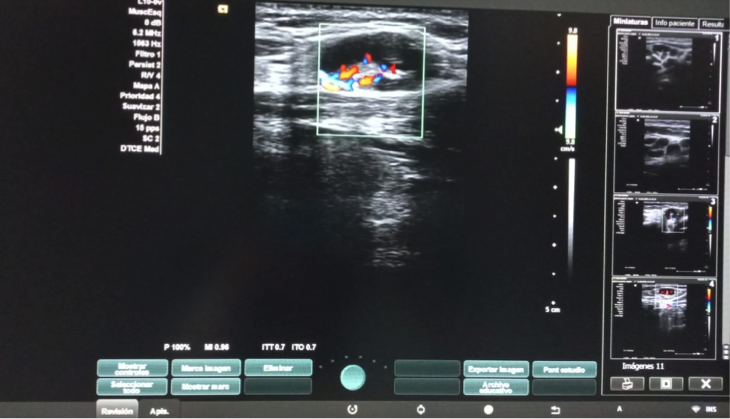

Hallazgos ecográficos

Dos adenopatías en territorio laterocervical derecho, con hilio central y doppler positivo, alguna con diámetro transversal superior al longitudinal, de probable origen reactivo y una adenopatía supraclavicular sin hilio central y con vascularización generalizada.